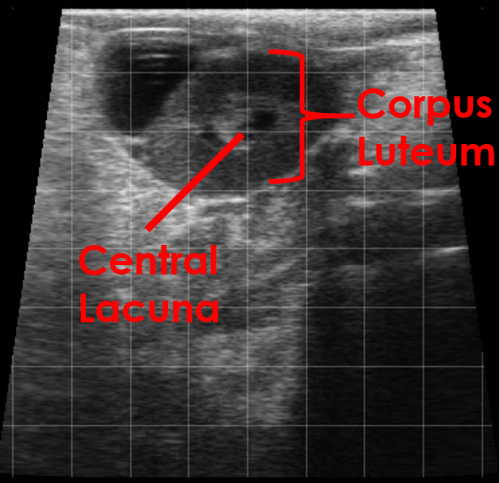

The corpus luteum appears as a defined area of hypoechoic tissue within the ovarian stroma.

A central lacuna (fluid-filled cavity) may be seen within a normal corpus luteum.